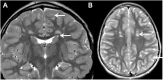

Relapsing demyelinating syndromes (RDS) in children encompass a diverse spectrum of entities including multiple sclerosis (MS) acute disseminated encephalomyelitis (ADEM), aquaporin-4 antibody associated neuromyelitis optica spectrum disorder (AQP4-NMOSD) and myelin oligodendrocyte glycoprotein antibody disease (MOG-AD). In addition to these, there are "antibody-negative" demyelinating syndromes which are yet to be fully characterized and defined. The paucity of specific biomarkers and overlap in clinical presentations makes the distinction between these disease entities difficult at initial presentation and, as such, there is a heavy reliance on magnetic resonance imaging (MRI) findings to satisfy the criteria for treatment initiation and optimization. Misdiagnosis is not uncommon and is usually related to the inaccurate application of criteria or failure to identify potential clinical and radiological mimics. It is also notable that there are instances where AQP4 and MOG antibody testing may be falsely negative during initial clinical episodes, further complicating the issue. This article illustrates the typical clinico-radiological phenotypes associated with the known pediatric RDS at presentation and describes the neuroimaging mimics of these using a pattern-based approach in the brain, optic nerves, and spinal cord. Practical guidance on key distinguishing features in the form of clinical and radiological red flags are incorporated. A subsection on clinical mimics with characteristic imaging patterns that assist in establishing alternative diagnoses is also included.